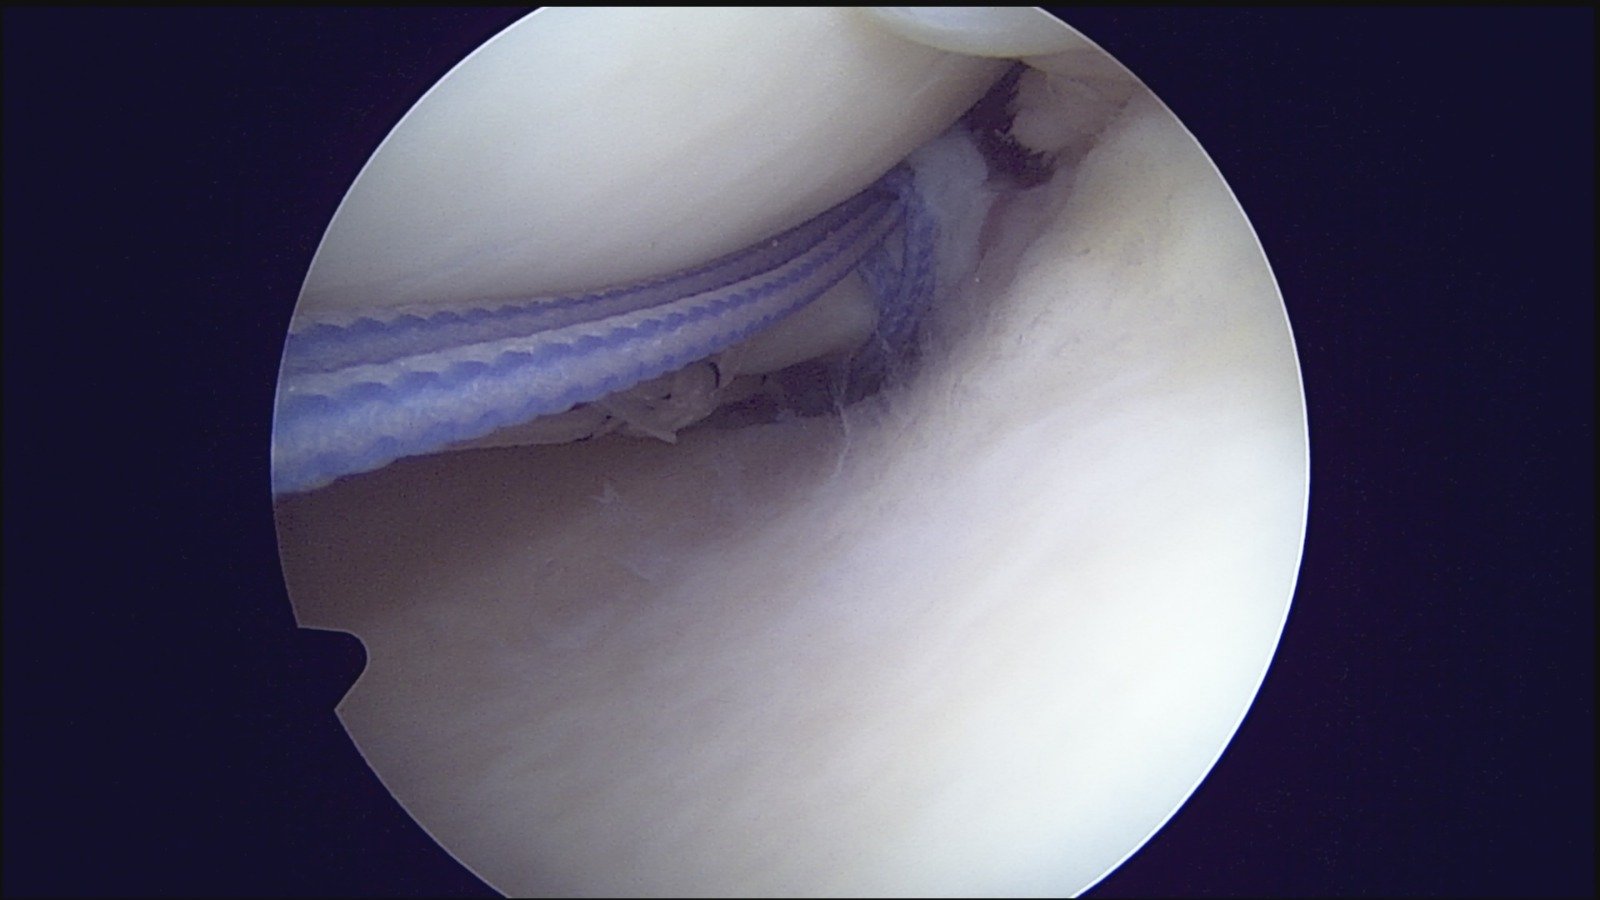

GalleryShoulder rotator cuff repair Meniscus root repair Meniscus repair Bankart repair for recurrent shoulder dislocation ACL reconstruction Machines Instruments